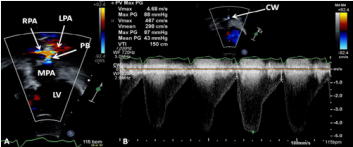

Figure 21 Selected echocardiographic video frames demonstrating pulmonary artery band (PAB) with narrow diameter of 2.9 mm by 2D (A) and by color flow (B) and a high gradient (81 mmHg) by continuous wave Doppler (C) are shown [69].

Echocardiographic and angiographic examples of some of the banding procedure are shown in Figures 21 to 23.